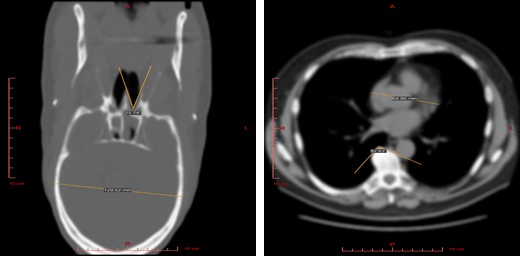

Measurement of distances, angles, and areas in 2D views.

Viewing sample in any standard projection.

2D Visualization¶

Use this mode to view raw data sections in different projections and to measure the linear and angular dimensions of fragments of this data.